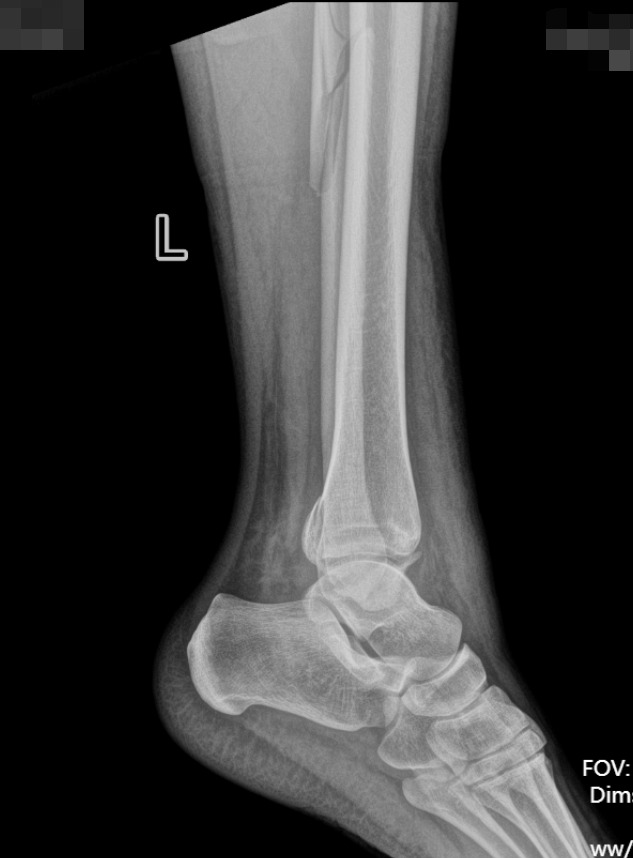

患者因意外受伤后踝关节疼痛、肿胀、无法行走,急诊就诊于成人ai 。

经检查确诊为旋前外旋 Ⅳ 度踝关节骨折,包含腓骨中段骨折、内踝骨折、后踝骨折及下胫腓联合分离,属于临床中结构复杂、稳定性破坏较严重的踝关节损伤。